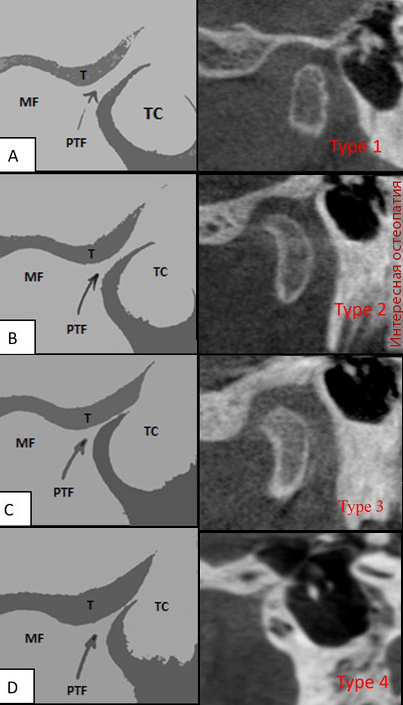

Рис. Варианты строения каменисто-барабанной щели. PTF — каменисто-барабанная щель, petrotympanic-fissure, T — височная кость, MF — нижнечелюстная ямка, TC — барабанная полость. источник